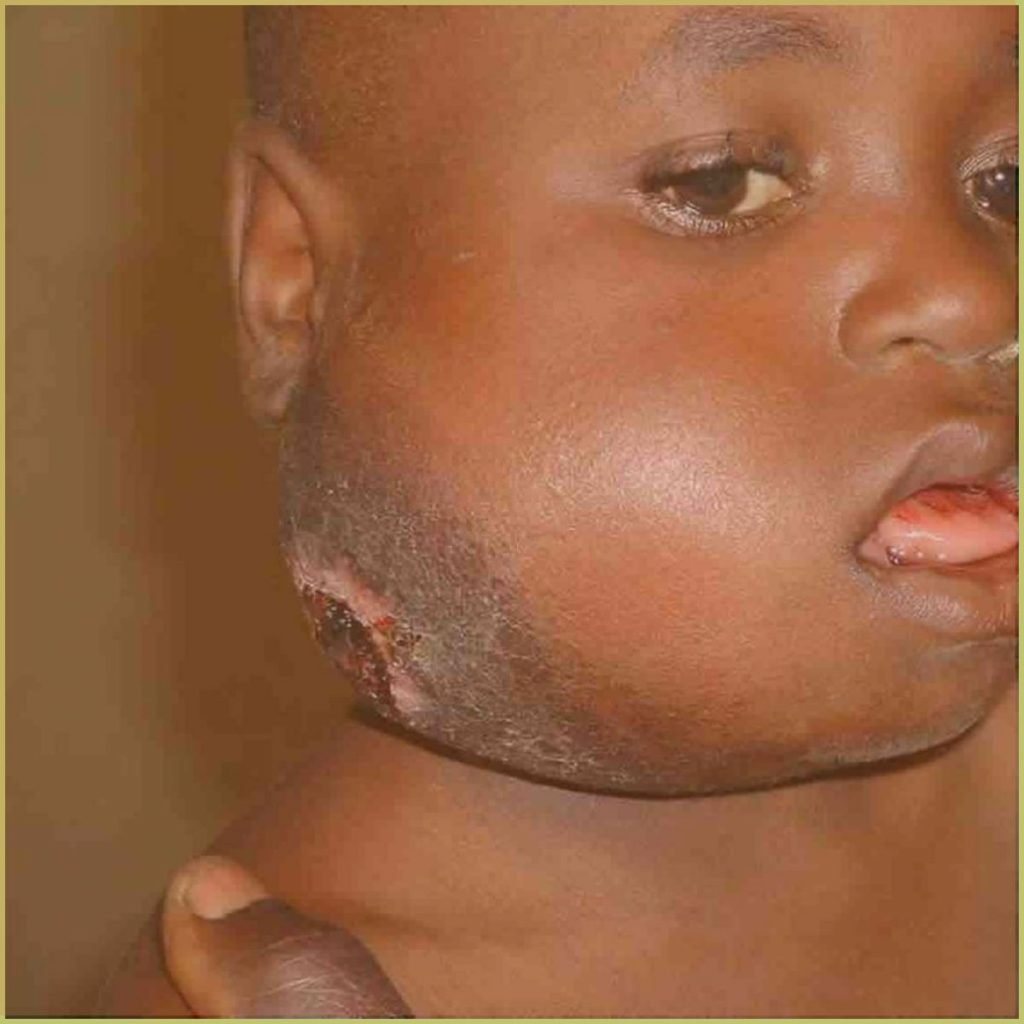

BURKITT LYMPHOMA

Burkitt Lymphoma (BL) is a highly aggressive B cell non-Hodgkin lymphoma associated with various genetic mutations (C-MYC, P53, TCF transcription factor) and exposure to certain pathogens (Epstein-Barr virus, Malaria). The endemic variant (African variant) most commonly affects the facial bones of children in malaria-endemic regions. The sporadic variant (non-African variant) is rarely associated with the Eptein-Barr virus and is more strongly associated with the abdominal (retroperitoneal) region. The common clinical presentation includes:

- Rapidly progressive facial tumor causing asymmetry.

- Quick dissemination to extranodal sites including CNS and bone marrow.

- Mainly affects the mandible (especially endemic variant).

- Proptosis, pain and paresthesia.